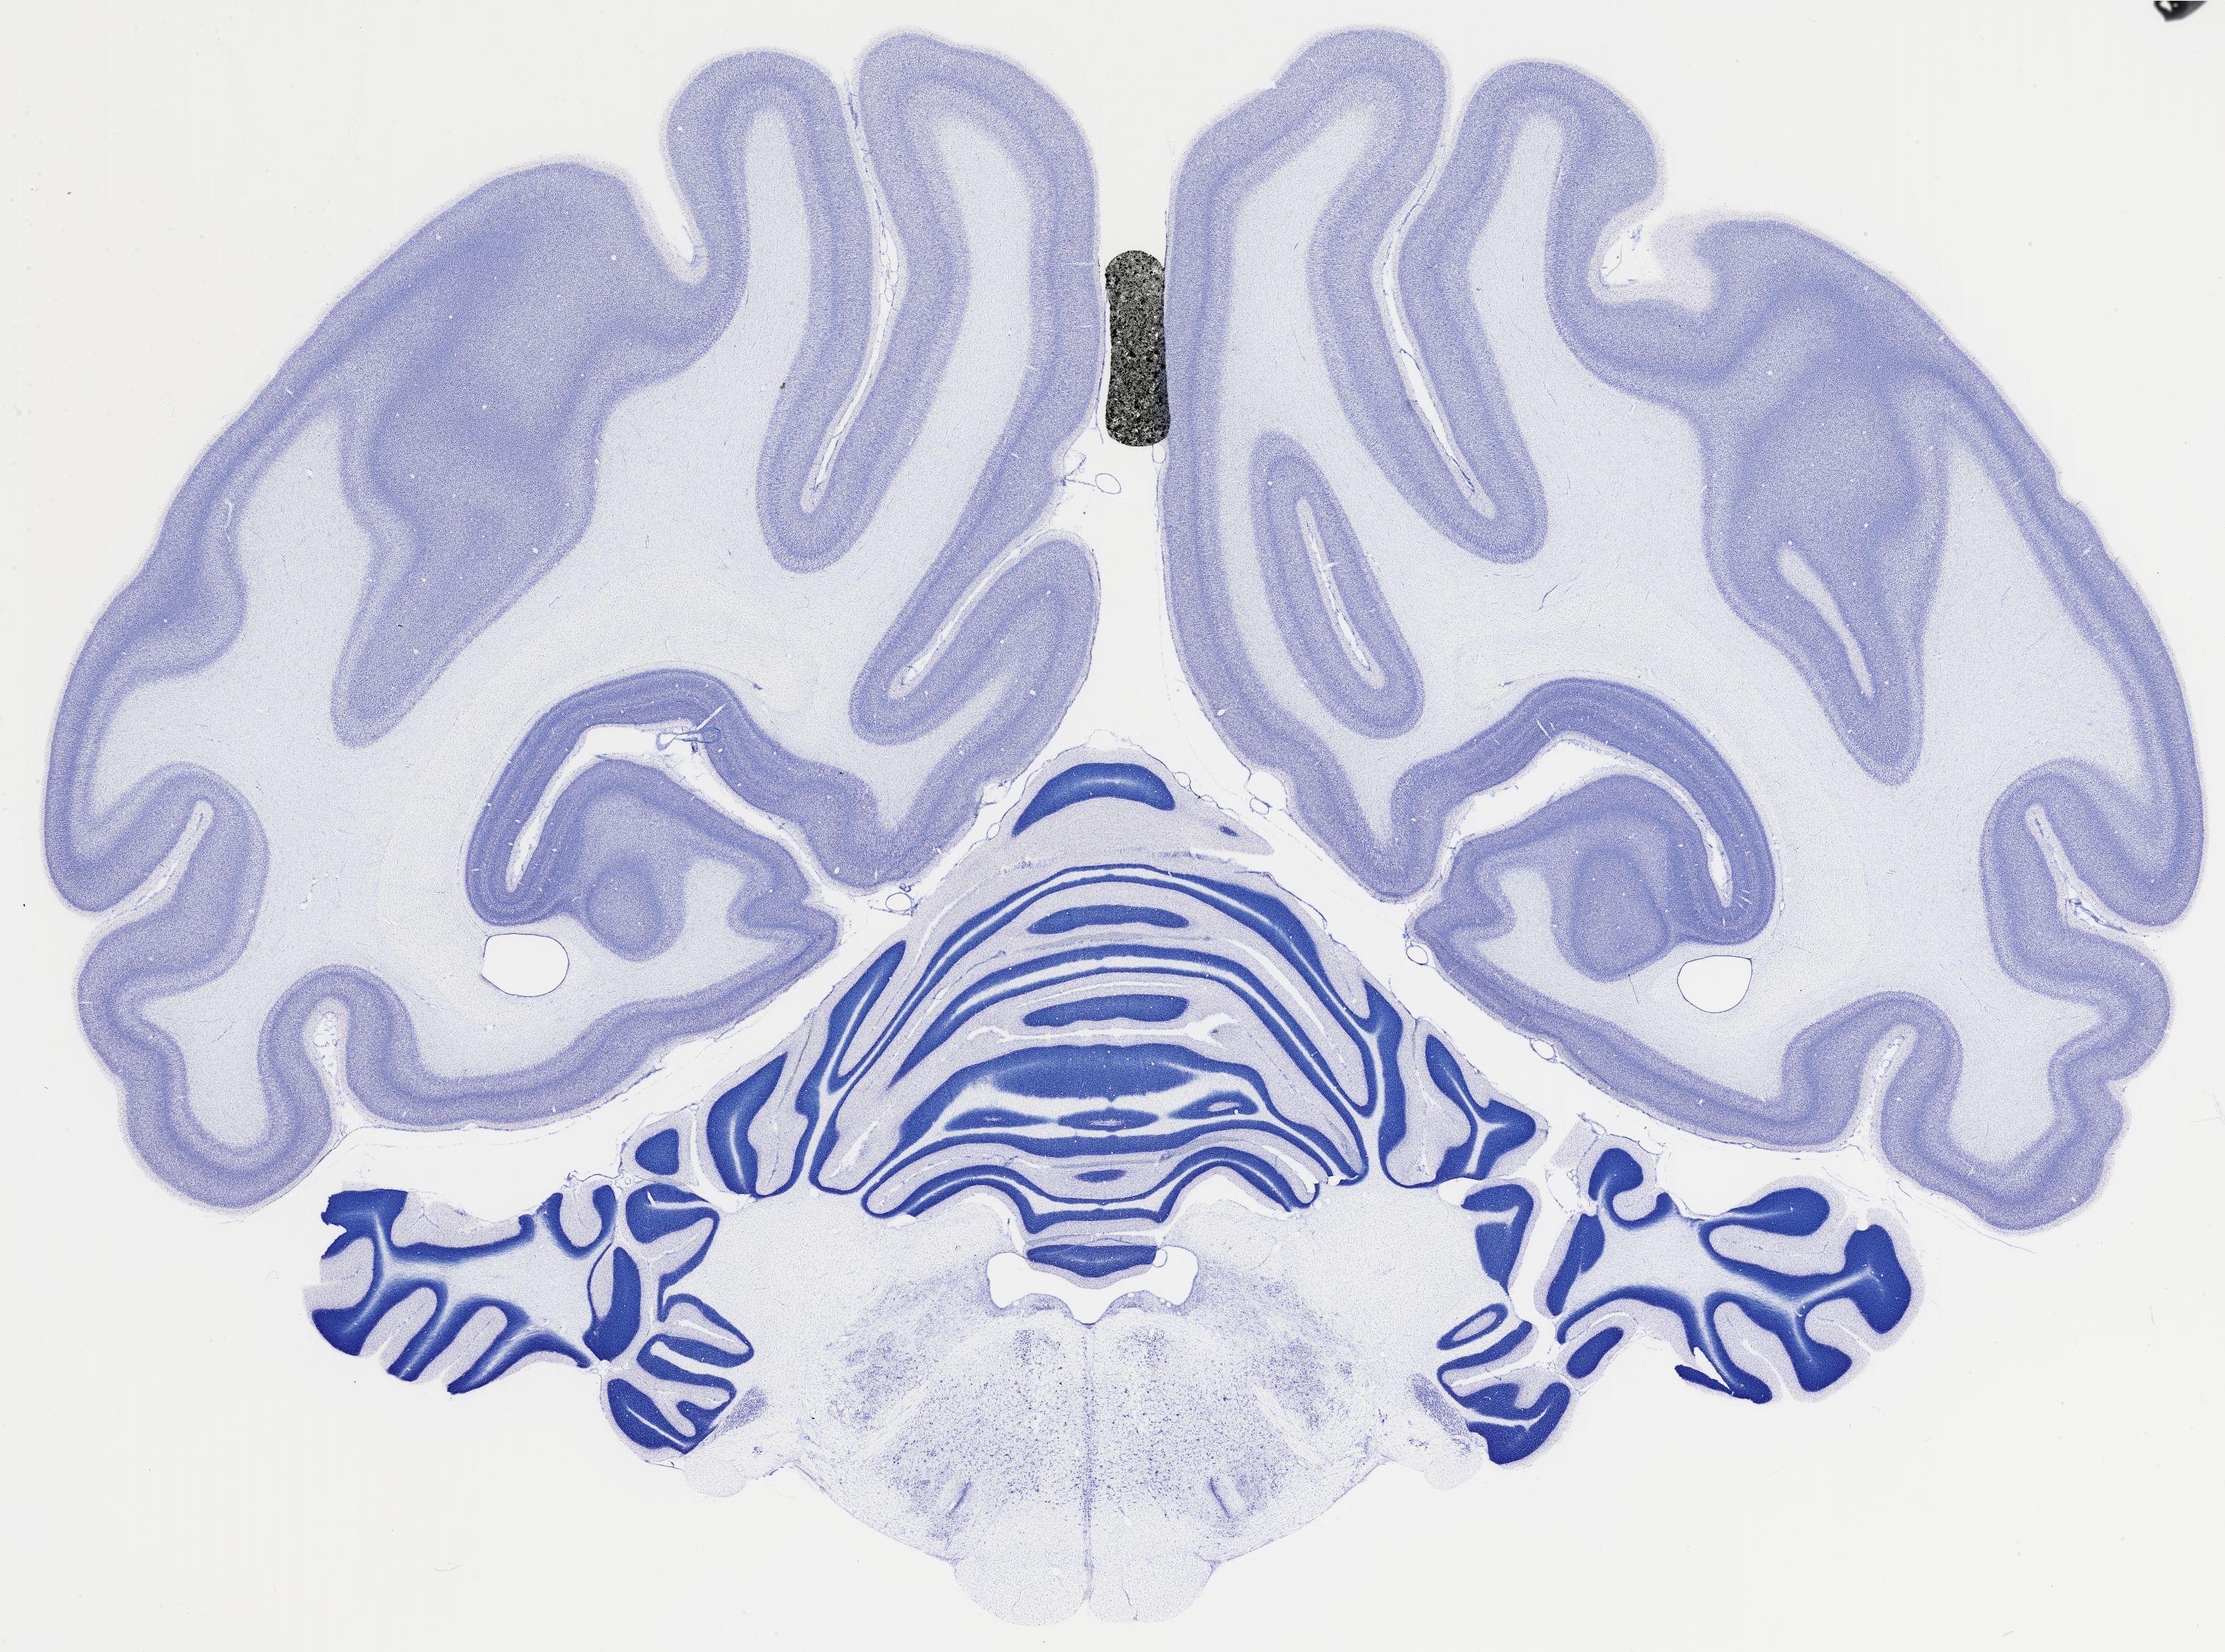

Datasets -> Chlorocebus Aethiops -> Nissl, coronal, histo, Whole-Brain, adult

[ Metadata ]   ·   Source: NeuroScience Associates

Displaying Sections 481 thru 520 of 740 Sections for this Dataset

thumbnail

522